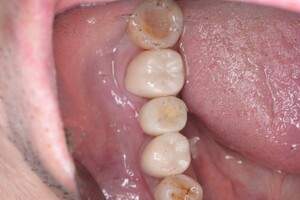

口腔内写真

- Befor

- After

| 年齢 | 50代・男性 |

| 主訴 | 左上7番 左下5番7番 |

| 治療内容 | ・インプラント埋入 ※1:GBR(骨造成)・・・骨再生誘導法。骨の高さや厚みを人工骨や人工膜などを使用し再生する方法 |

| 治療費 | 合計:1,809,500円(税込) ■内訳 ・左上7番 ・左下5番7番 |

| 治療期間 | 左上7番約1年 左下5番7番約10ヵ月 |

| 治療方針 | 左上7番は昔他院で被せものをしており、被せものの中が歯ぐきの中まで虫歯になっていたため抜歯せざるを得ない状態だった。抜歯と同時に骨造成を行い、骨が出来るまで4ヵ月待ってからインプラントを埋入した。 ※2ポンティック・・・歯のない部分を補うダミーの歯。 |

| 担当者所見 | 元々金属の被せものが多く入っていたため、2次カリエス※3が多かった。今回は金属ではなく、ジルコニアを使用し、2次カリエスにならないよう、患者様にはブラッシング指導とメンテナンスの重要性をお伝えした。 ※3二次カリエス・・・詰め物や被せものを入れた歯が虫歯になること。 |